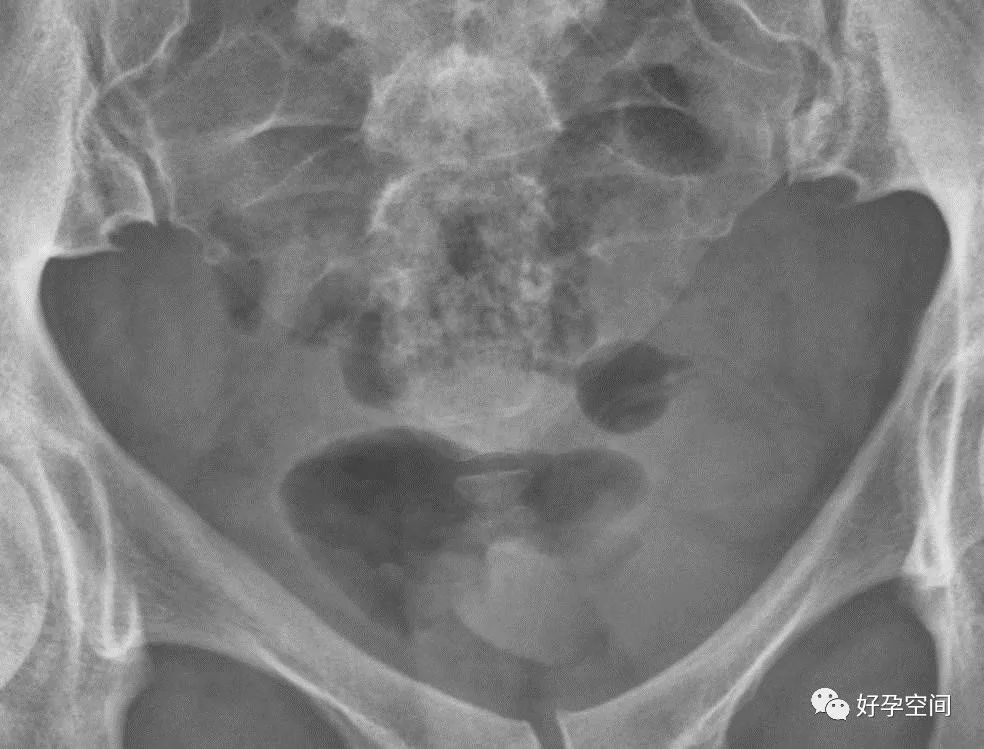

2、碘油残留

平片,盆腔内可见片状、点状及不规则形高密度影

3、骨斑点症

骨盆诸骨均可见多发小圆形高密度影

4、骶髂关节炎

双侧骶髂关节周围骨质密度增高

5、盆腔陈旧性结核钙化灶

盆腔内见多个片状及点状高密度钙化影

6、子宫肌瘤钙化

盆腔内见类圆形蛋壳样高密度影

7、畸胎瘤钙化

盆腔内见牙齿状高密度钙化影